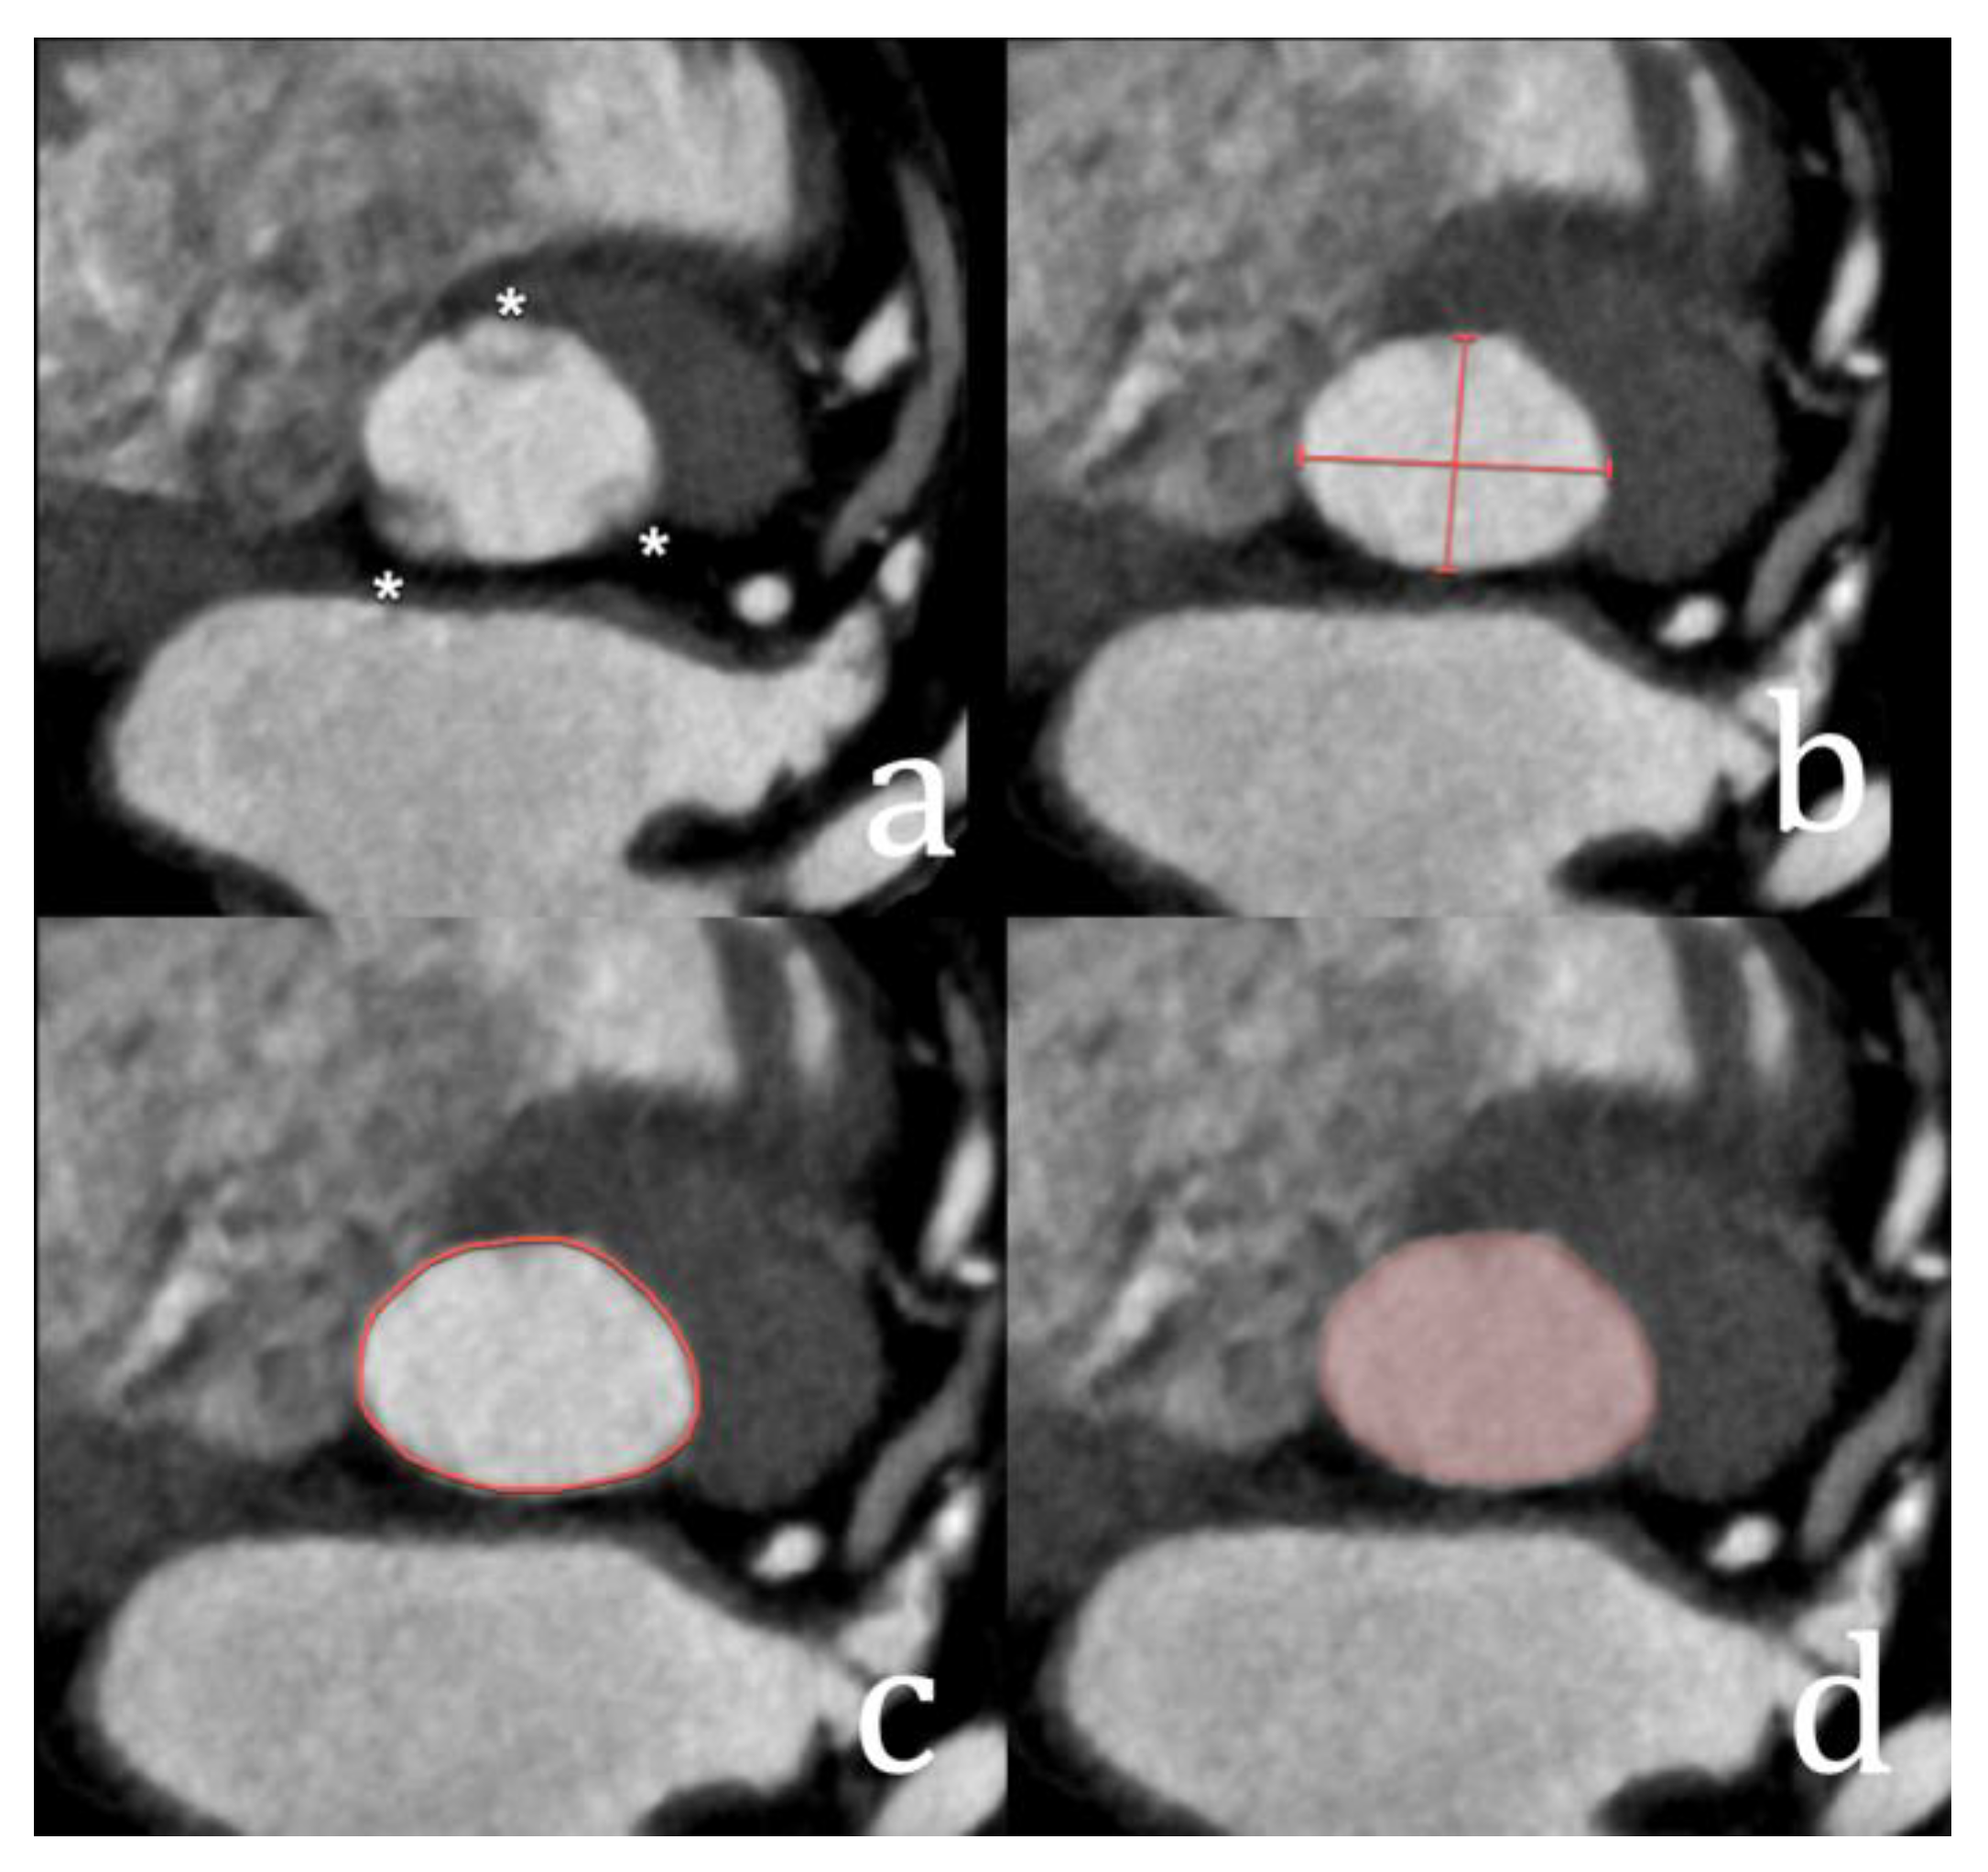

3. Transcatheter Aortic Valve Replacement

| Aortic valve calcification | Quantification and distribution of leaflet calcification | The Agatston score is used to quantify leaflet calcifications. This is not routine and typically reserved for low-flow low-gradient cases with inconclusive echocardiography results. |

- Pawade, T.; Sheth, T.; Guzzetti, E.; Dweck, M.R.; Clavel, M.-A. Why and How to Measure Aortic Valve Calcification in Patients With Aortic Stenosis. JACC Cardiovasc. Imaging 2019, 12, 1835–1848. [Google Scholar] [CrossRef]

- Wang, T.K.M.; Flamm, S.D.; Schoenhagen, P.; Griffin, B.P.; Rodriguez, L.L.; Grimm, R.A.; Xu, B. Diagnostic and Prognostic Performance of Aortic Valve Calcium Score with Cardiac CT for Aortic Stenosis: A Meta-Analysis. Radiol. Cardiothorac. Imaging 2021, 3, e210075. [Google Scholar] [CrossRef]